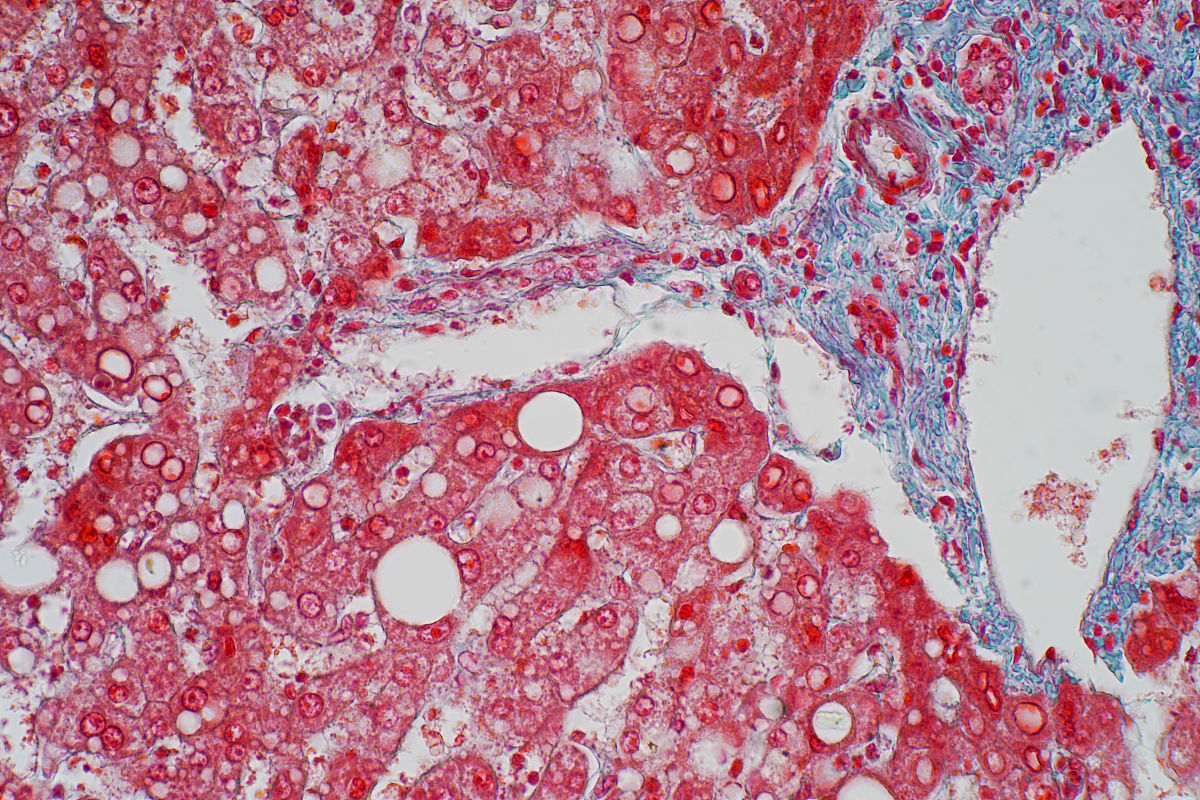

Iga肾病发展出fsgs 是不是比较严重

是的,FSGS是一种比较严重的肾病。它是一种肾小球疾病,会导致肾小球滤过功能受损,导致蛋白尿、肾功能衰竭等严重后果。FSGS的治疗比较困难,需要长期的药物治疗和监测,有些病人可能需要肾移植才能恢复正常的肾功能。